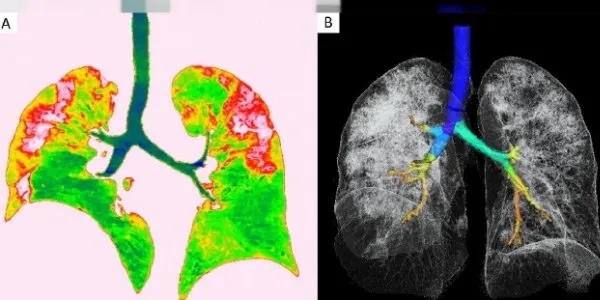

Prof. Dr. Özen, "Bireylerin genetik yatkınlığı ve geçmişi, bu hastalığın seyri konusunda önemli ipuçları veriyor. Kovid-19'u çok ağır geçiren, yoğun bakım tedavisi görmek durumunda kalan hastaların bir bölümünde doğuştan gelen genetik mutasyonlara rastlandığı ortaya konuldu. Bu hastalarda vücudu virüslerden koruyan ve 10'dan fazla proteinden oluşan Tip 1 İnterferon bulunmadığı belirtildi.

INTERFERON VÜCUDA BİR SALDIRI OLDUĞUNDA ÜRETİLİYOR

Vücuttaki görevi virüsün çoğalmasını durdurmak olan Tip 1 İnterferon, enfeksiyonu tespit ettiği anda bağışıklık sistemi tarafından üretiliyor.

Hastalarda koronavirüsün ağır geçirilmesinin nedeni de Tip 1 İnterferon sinyal ağının bozulmasından kaynaklanıyor. Kovid- 19 Genetik Yatkınlık Testi ile bunu tespit edebiliyoruz" dedi.